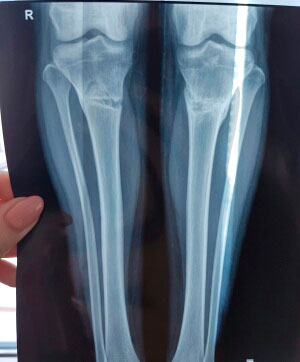

Дата операции - 12.10.2017г.

Дата снятия аппаратов 22.01.2018г.

Срок лечения 100 дней.